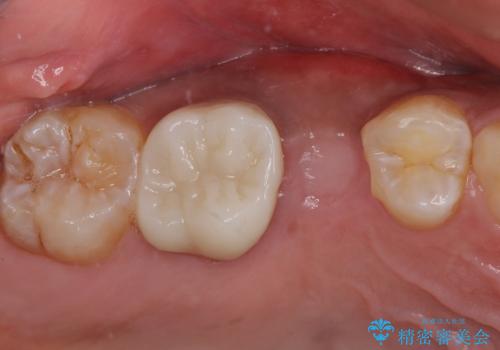

レントゲン撮影により、右上奥歯が折れていることが分かりました。

患者様自身も何となく違和感を覚えていたとのことで、インプラント補綴治療を行うこととしました。

破折して抜歯が必要となった歯の後ろの歯は、根管治療が必要な状態であったので、根管治療を行い、矯正治療後にインプラント部の補綴治療と同時にセラミッククラウンを装着しました。